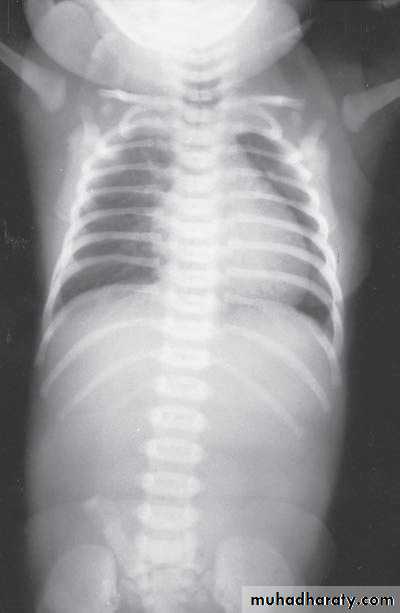

Congenital lober emphysema